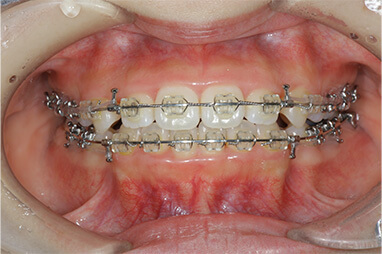

セラミックインレーの装着時には写真のようにラバーダムというゴムのシートを使うことにより接着力が増します。

接着力が増すと虫歯の再発率を減らすことにつながります。